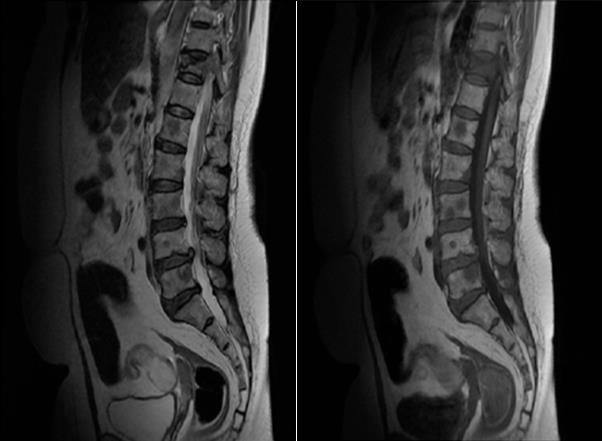

Магнитно-резонансная томография при метастазах в кости хорошо выявляет следующие анатомические признаки:

В режиме Т1 определяется гипоинтенсивный сигнал от участков костного мозга, что указывает на замещение жировой ткани опухолевыми клетками.

В режиме Т2 визуализируется гиперинтенсивный сигнал в зоне метастатического поражения, особенно при остеолитических очагах, с неравномерным распространением по губчатому веществу.

В режиме с подавлением сигнала от жира чётко выделяются очаги патологического сигнала на фоне нормального костного мозга, что повышает контрастность поражения.

В режиме с контрастированием выявляется гетерогенное усиление сигнала, особенно в опухолях с выраженной васкуляризацией, а также определяется перикостальное распространение.

Определяются дополнительные аспекты, включая отёк окружающих тканей, патологические переломы, реактивные изменения надкостницы и вовлечение мягких тканей.